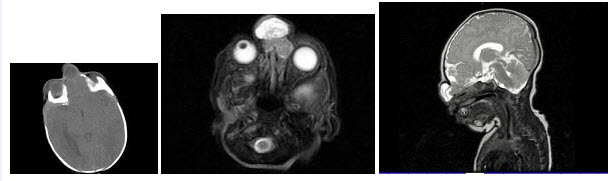

145、单项选择题

出生2天的男婴,鼻根部眉间正中有一肿块,CT检查如图,最可能的诊断是()

A.蛛网膜囊肿

B.脑膨出

C.硬膜外囊肿

D.鼻息肉

E.鼻咽癌